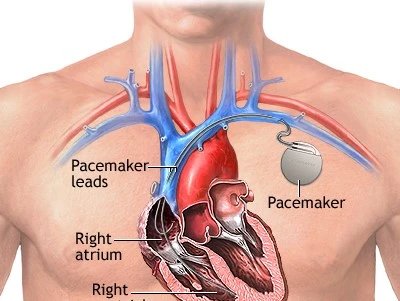

Cardiac Electrophysiologist with expertise in the field of cardiac arrhythmias. Areas of specialisation include pacemaker and heart failure device (CRT / defibrillator) implantations, electrophysiological studies, and radiofrequency ablation.

Committed to personalised, evidence-based cardiac care — taking the time to explain every diagnosis and treatment option clearly to patients and their families.